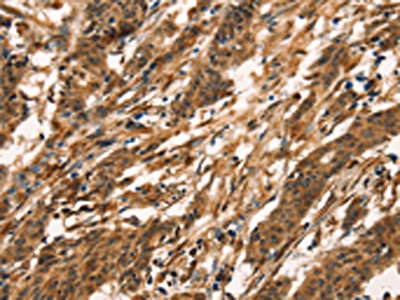

The image on the left is immunohistochemistry of paraffin-embedded Human liver cancer tissue using CSB-PA911316(KLRC1 Antibody) at dilution 1/30, on the right is treated with fusion protein. (Original magnification: ×200)

The image on the left is immunohistochemistry of paraffin-embedded Human gastric cancer tissue using CSB-PA911316(KLRC1 Antibody) at dilution 1/30, on the right is treated with fusion protein. (Original magnification: ×200)